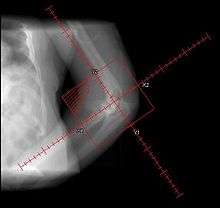

During the early stage, an x-ray will not be helpful because there is no calcium in the matrix. (In an acute episode which is not treated, it will be 3– 4 weeks after onset before the x-ray is positive.) Early laboratory tests are not very helpful. Alkaline phosphatase will be elevated at some point, but initially may be only slightly elevated, rising later to a high value for a short time. Unless weekly tests are done, this peak value may not be detected. It is not useful in patients who have had fractures or spine fusion recently, as they will cause elevations.

The only definitive diagnostic test in the early acute stage is a bone scan, which will show hetertopic ossification 7 – 10 days earlier than an x-ray. The three-phase bone scan may be the most sensitive method of detecting early heterotopic bone formation. However, an abnormality detected in the early phase may not progress to the formation of. heterotopic bone. Another finding, often misinterpreted as early heterotopic bone formation, is an increased (early) uptake around the knees or the ankles in a patient with a very recent spinal cord injury. It is not clear exactly what this means, because these patients do not develop heterotopic bone formation. It has been hypothesized that this may be related to the autonomic nervous system and its control over circulation.[2]